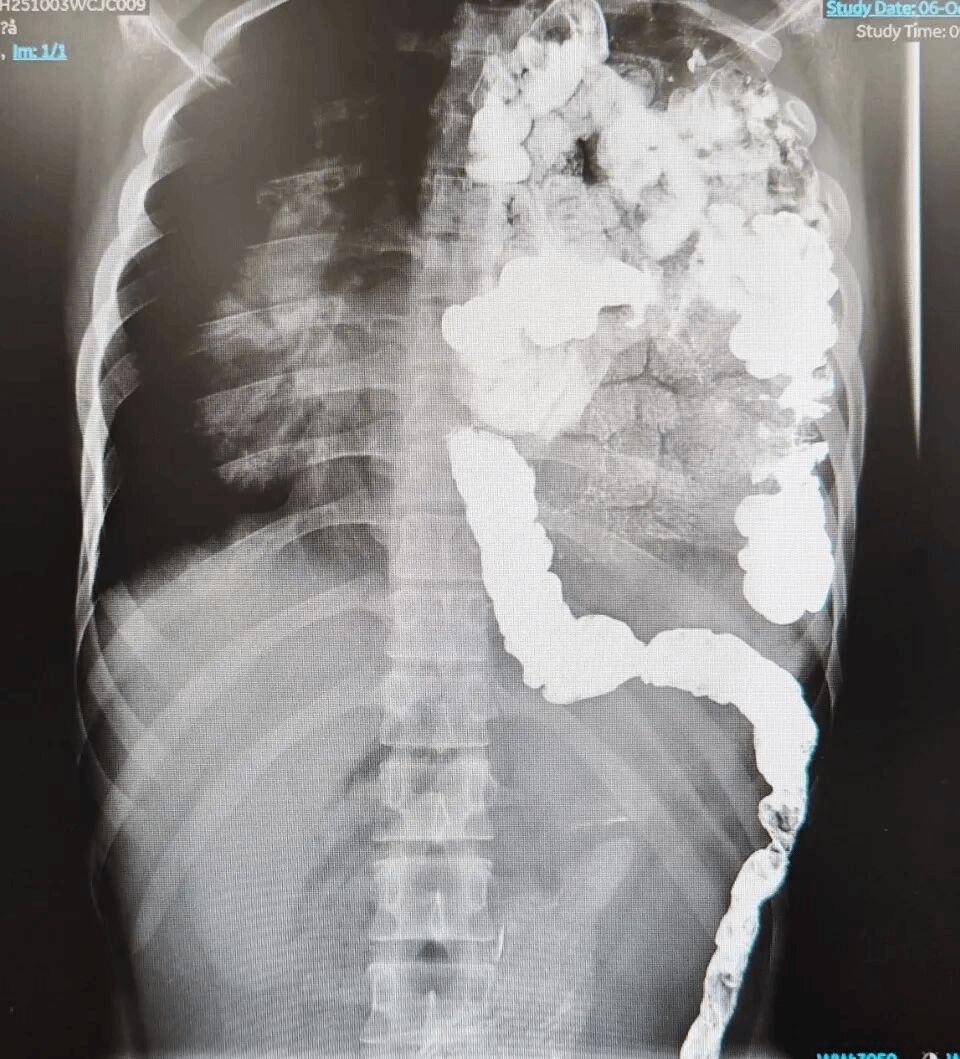

“几乎所有肠子都跑到胸腔里了,严重挤压着心脏和左肺。”重庆医科大学附属儿童医院胸心外科李洪波主任医师指着患儿的影像图说,“我们也是第一次接诊到如此大年龄的先天性膈疝患儿,先天性膈疝在小儿胸心外科疾病中并不少见,诊断也不复杂,目前产前即可诊断,一般出生后就需要处理,以往我们接诊的先天性后外侧膈疝患儿绝大多数是新生儿或婴幼儿年龄,最大不过四五岁。”

“按计划,先进行胸腔镜探查,发现左侧膈肌缺损直径约为8cm,所有小肠、绝大部分结肠都疝入并充满整个胸腔。”李洪波主任医师说,由于肠系膜与疝孔边缘粘连,且肠系膜异常肥厚,虽然膈肌“洞口”不小,但无法通过胸腔镜的微创方式将肠管从“洞口”返纳腹腔。

于是,医生通过胸部小切口松解局部粘连,人为扩大“洞口”,但仍然无法将肠管送回腹腔。团队加用腹腔镜探查,尝试从腹腔“拽”+胸腔“推”的方法,但已在胸腔发育17年的粗大肠管及异常肥厚的肠系膜仍然不能返纳腹腔。

最终,李洪波主任医师和普外新生儿科刘清爽副主任医师决定采取胸腹部联合切口,才把肠管“赶回”腹腔,利用特殊材料重建膈肌补上了大洞。